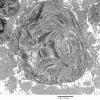

PERIPHERAL NEUROPATHY

4 AXONAL DEGENERATION

3 Electron Microscopy (3)